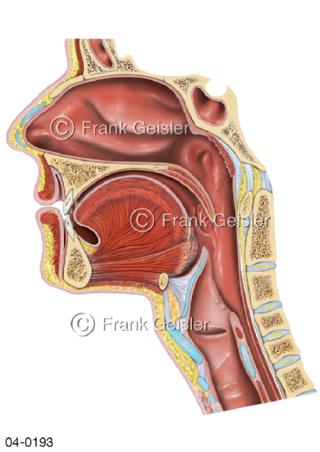

Bildergalerie Topografie Organe

Bilder zur topografischen Anatomie, die Lage der Organe und die Strukturen nach ihren räumlichen Lagebeziehungen zueinander, Übersicht der inneren Organe im Kopf und im Rumpf, Topografie der Organe im Brustraum (Thorax) und im Bauchraum (Abdomen)